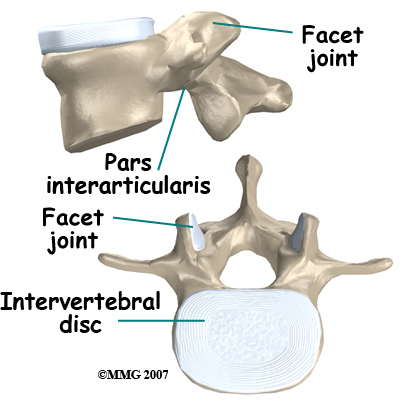

The spine is made up of a column of bones. A round block of bone, called a vertebral body, forms the biggest portion of each segment, or vertebrae. A bony ring attaches to the back of the vertebral body, forming a canal for the spinal cord.

Facet joints are small joints on either side of the spine that allow motion. As the bones of the spine interlock, a facet joint is formed. Each vertebra will form two facet joints, on either side. There is a pair at the top and a pair at the bottom of each vertebra. The area of the vertebra that connects the large body of the vertebra to the facet joints is called the pars articularis or pedicle.

The part between the two sets of facet joints is the lamina.

The spine is made up of a column of bones. A round block of bone, called a vertebral body, forms the biggest portion of each segment, or vertebrae. A bony ring attaches to the back of the vertebral body, forming a canal for the spinal cord.

Facet joints are small joints on either side of the spine that allow motion. As the bones of the spine interlock, a facet joint is formed. Each vertebra will form two facet joints, on either side. There is a pair at the top and a pair at the bottom of each vertebra. The area of the vertebra that connects the large body of the vertebra to the facet joints is called the pars articularis or pedicle.

The part between the two sets of facet joints is the lamina.

Intervertebral discs form a cushion between the round blocks of bone making up the vertebral body. The area where the disc attaches to the vertebral body is called an end plate. Discs are a collection of tough tissue similar to a ligament. They are filled with fluid when healthy.